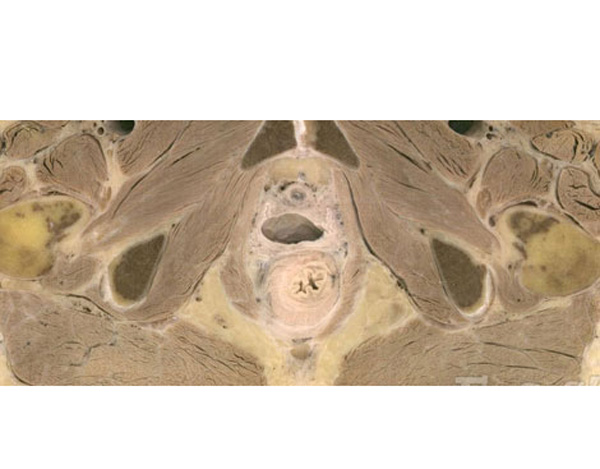

女性生殖器官医学切片(2)

女性生殖器官医学切片